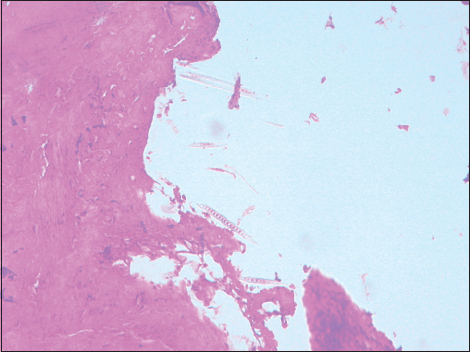

Figure 8: Contaminant artifact in a section of the bone marrow, ×100